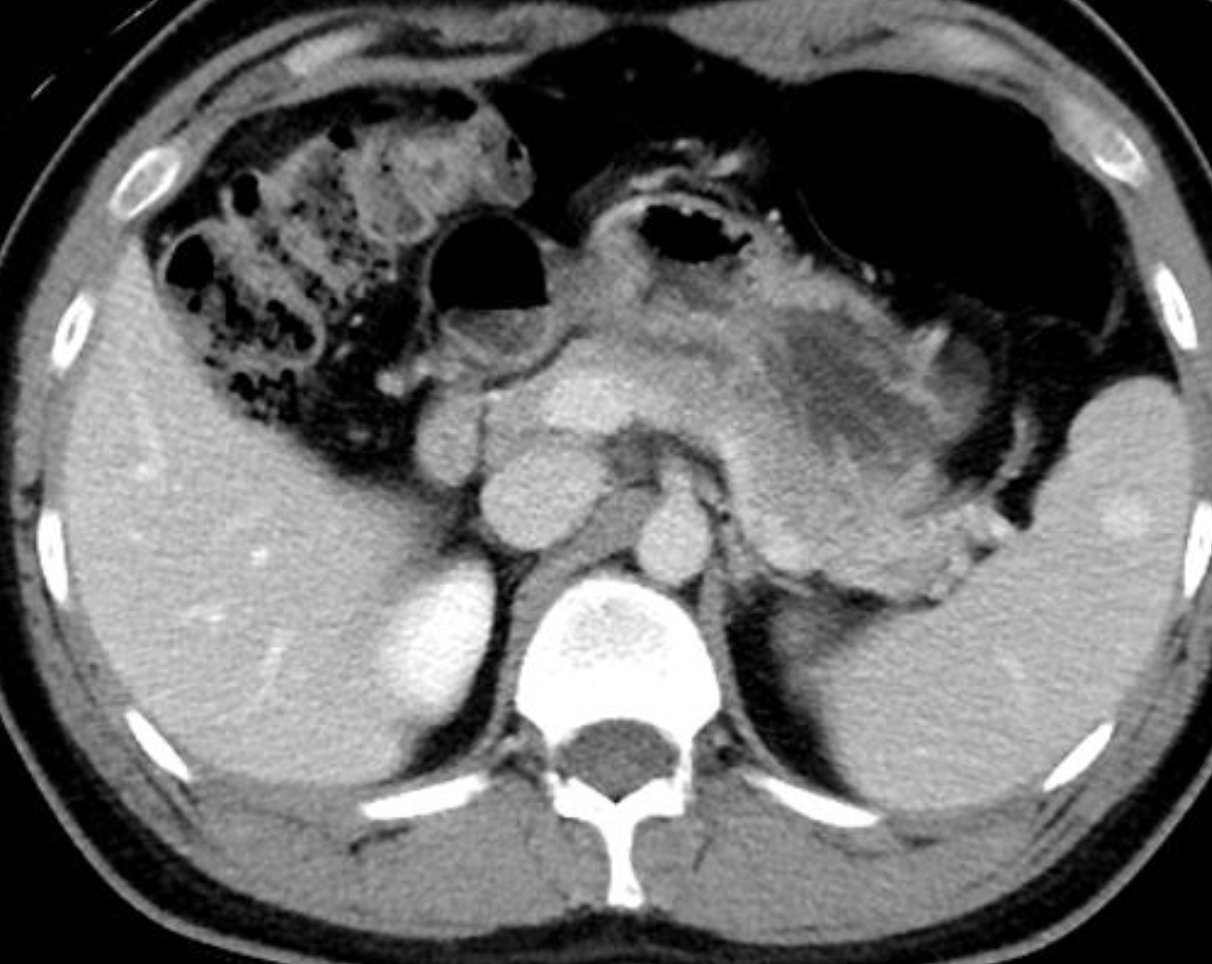

Extensive splenic lacerations extending to the hilum with areas of devascularisation. No evidence of active bleeding or pseudo-aneurysm. There is extensive haemoperitoneum throughout the abdominopelvic cavity. Cholecystectomy clips are noted along with extrahepatic and first order intrahepatic duct dilatation. Liver is uninjured. Adrenal glands, kidneys and pancreas are uninjured. Bowel is unremarkable. Lung bases are clear. No bony injury identified.

Conclusion:

AAST grade IV splenic injury with extensive haemoperitoneum.

Case Discussion

Further history obtained (after the CT) revealed a fall from 1.5 metres. Patient proceeded to successful splenic embolisation.